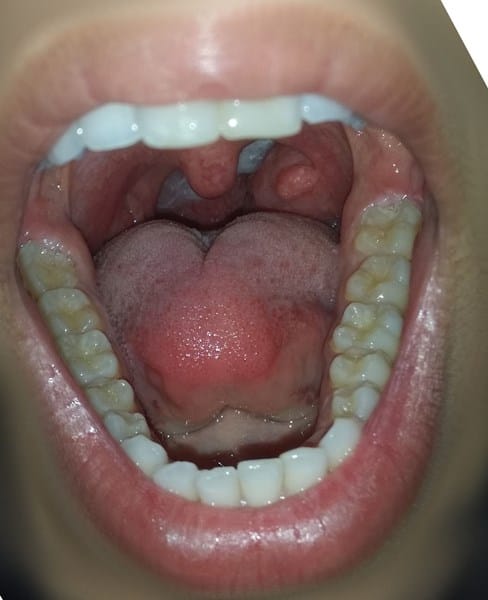

Amígdala izquierda grande ¿Operarse o no?

Tengo la amígdala izquierda bastante grande, siempre la he tenido desde pequeño (creo que ha crecido conmigo) para ya me esta molestando demasiado.

La derecha no la siento, pero la izquierda en todo momento, aunque no esté inflamada.

Siento una presión en la garganta y me molesta algo al tragar, lo suficiente para querer quitármela. He ido al médico, me la vio durante 5segundos y me dijo que la tenía grande, que es lo que hay, que las amígdalas nos protegen de cosas peores.

Por cierto, tengo un bulto en ella, el médico me dijo que es una formación, que no es nada, pero a veces me pica.

Adjunto foto

¿Qué opináis? ¿No me está quitando algo de respiración? ¿Es posible que me quite ganas de comer?